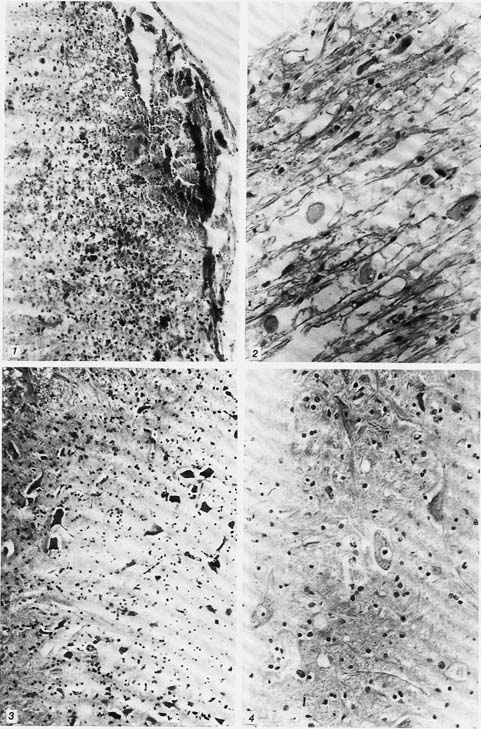

рис. 5-8

Рис. 5. Очаговые дистрофические изменения нейронов в зоне параконтузионного очага спинного мозга различной степени выраженности на 14-е сутки (II серия). Окраска по Нисслю. Ув. 280.

Рис. 6. Умеренные изменения нейронов в задних рогах спинного мозга на 5-е сутки (III серия). Окраска по Нисслю. Ув. 280.

Рис. 7. Тяжелые и умеренные обратимые формы дистрофических изменений нейронов на 14-е сутки (III серия). Окраска по Нисслю. Ув. 140.

Рис. 8. Контузионный очаг в спинном мозге отграничен грануляционной тканью на 14-е сутки. (III серия). Окраска по Ван-Гнзон. Ув. 70.

К 14-м суткам наблюдалась активизация восстановительных процессов: отграничение внутримозговых и подпаутинных кровоизлияний фибро-ретикулярной тканью, значительный регресс отека ткани серого и белого вещества спинного мозга. В параконтузионной зоне в нейронах задних рогов на фоне необратимо измененных нейронов определялись легкие и умеренные дистрофически измененные нервные клетки. Ткань мозга была гиперемирована за счет дополнительно функционирующих капилляров (рис. 4, 5).

На 5-е сутки различия с контролем особенно выраженны. Субдуральные и субарахноидальные кровоизлияния, как правило, хорошо отграничивались ангиоматозной грануляционной тканью с макрофагальной реакцией. Особенно отличалось состояние микроциркуляторного русла: капилляры были полнокровны, практически не содержали описанных в контроле сладж-феноменов. Уменьшался периваскулярный отек ткани. В параконтузионной зоне спинного мозга в нейронах задних рогов преобладали легкие и умеренные дистрофические формы измененных нейронов, что указывало на положительное влияние лазерного облучения (рис. 6).

К 14-м суткам очаги повреждения и кровоизлияний были отграничены обильно васкуляризо-ванной грануляционной тканью с перифокальной пролиферацией глиомезенхимальных элементов. Ткань мозга выглядит полнокровнее, чем в контроле, преимущественно за счет повышенного числа функционирующих капилляров. В параконтузионной зоне преобладали нейроны без признаков повреждения в легкой степени дистрофии, на фоне которых были более заметны немногочисленные формы грубо поврежденных нервных клеток (рис. 7, 8).